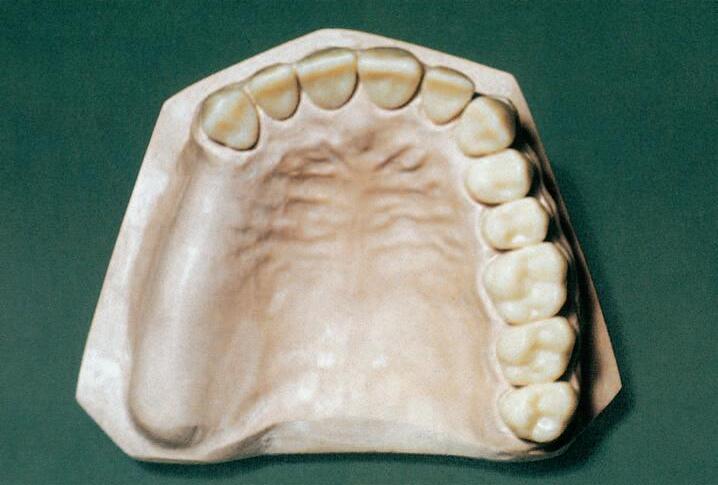

Obr.1 Chrupsmezerami

Obr.2 Velkámezerado4zubù

Obr.3 Jednostrannìzkrácenýzubníoblouk

Obr.4 Oboustrannìzkrácenýzubníoblouk

Obr.5 Ojedinìlézubynebojejichskupiny

Obr.9 Studijnímodelpøedortodontickouterapiívdospìlosti

Obr.10 Stavzubníhoobloukupøedprotetickýmošetøením